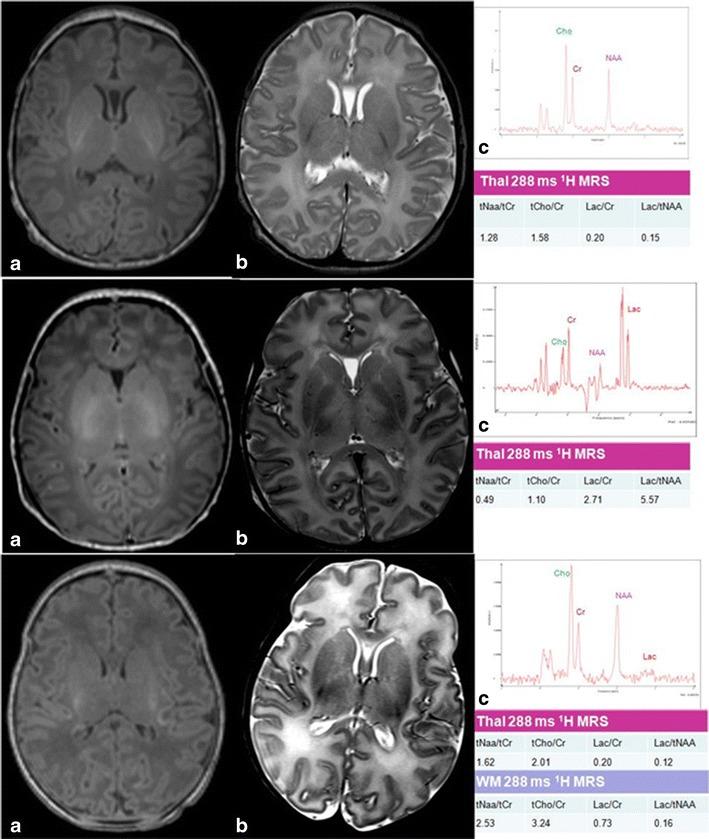

Encephalopathy consequent on perinatal hypoxia-ischemia occurs in 1-3 per 1,000 term births in the UK and frequently leads to serious and tragic consequences that devastate lives and families, with huge financial burdens for society. Although the recent introduction of cooling represents a significant advance, only 40% survive with normal neurodevelopmental function. There is thus a significant unmet need for novel, safe, and effective therapies to optimize brain protection following brain injury around birth. The Na⁺/H⁺ exchanger (NHE) is a membrane protein present in many mammalian cell types. It is involved in regulating intracellular pH and cell volume. NHE1 is the most abundant isoform in the central nervous system and plays a role in cerebral damage after hypoxia-ischemia. Excessive NHE activation during hypoxia-ischemia leads to intracellular Na⁺ overload, which subsequently promotes Ca²⁺ entry via reversal of the Na⁺/Ca²⁺ exchanger. Increased cytosolic Ca²⁺ then triggers the neurotoxic cascade. Activation of NHE also leads to rapid normalization of pHi and an alkaline shift in pHi. This rapid recovery of brain intracellular pH has been termed pH paradox as, rather than causing cells to recover, this rapid return to normal and overshoot to alkaline values is deleterious to cell survival. Brain pHi changes are closely involved in the control of cell death after injury: an alkalosis enhances excitability while a mild acidosis has the opposite effect. We have observed a brain alkalosis in 78 babies with neonatal encephalopathy serially studied using phosphorus-31 magnetic resonance spectroscopy during the first year after birth (151 studies throughout the year including 56 studies of 50 infants during the first 2 weeks after birth). An alkaline brain pHi was associated with severely impaired outcome; the degree of brain alkalosis was related to the severity of brain injury on MRI and brain lactate concentration; and a persistence of an alkaline brain pHi was associated with cerebral atrophy on MRI. Experimental animal models of hypoxia-ischemia show that NHE inhibitors are neuroprotective. Here, we review the published data on brain pHi in neonatal encephalopathy and the experimental studies of NHE inhibition and neuroprotection following hypoxia-ischemia.